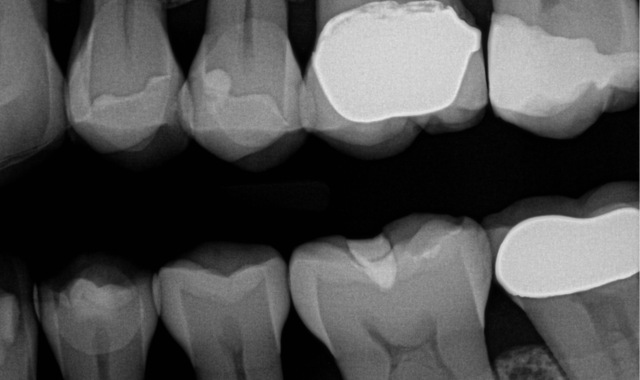

Fig. 1

Fig. 2

A 50-year-old female patient presented for replacement of a fracture and decay in an existing composite restoration (Figs. 1-2). While crowns or onlays would be the typical treatment of choice in our office, the patient will need to put off receiving indirect restorations for a couple years. It was decided that due to the depth of the existing restorations and the recurrent caries present, it would be wisest to perform caries control for the teeth.

A post-operative picture and radiograph were taken to confirm ideal restoration placement with sealed proximal margins and a void-free restoration (Figs. 14-15).

Fig. 14

Fig. 15